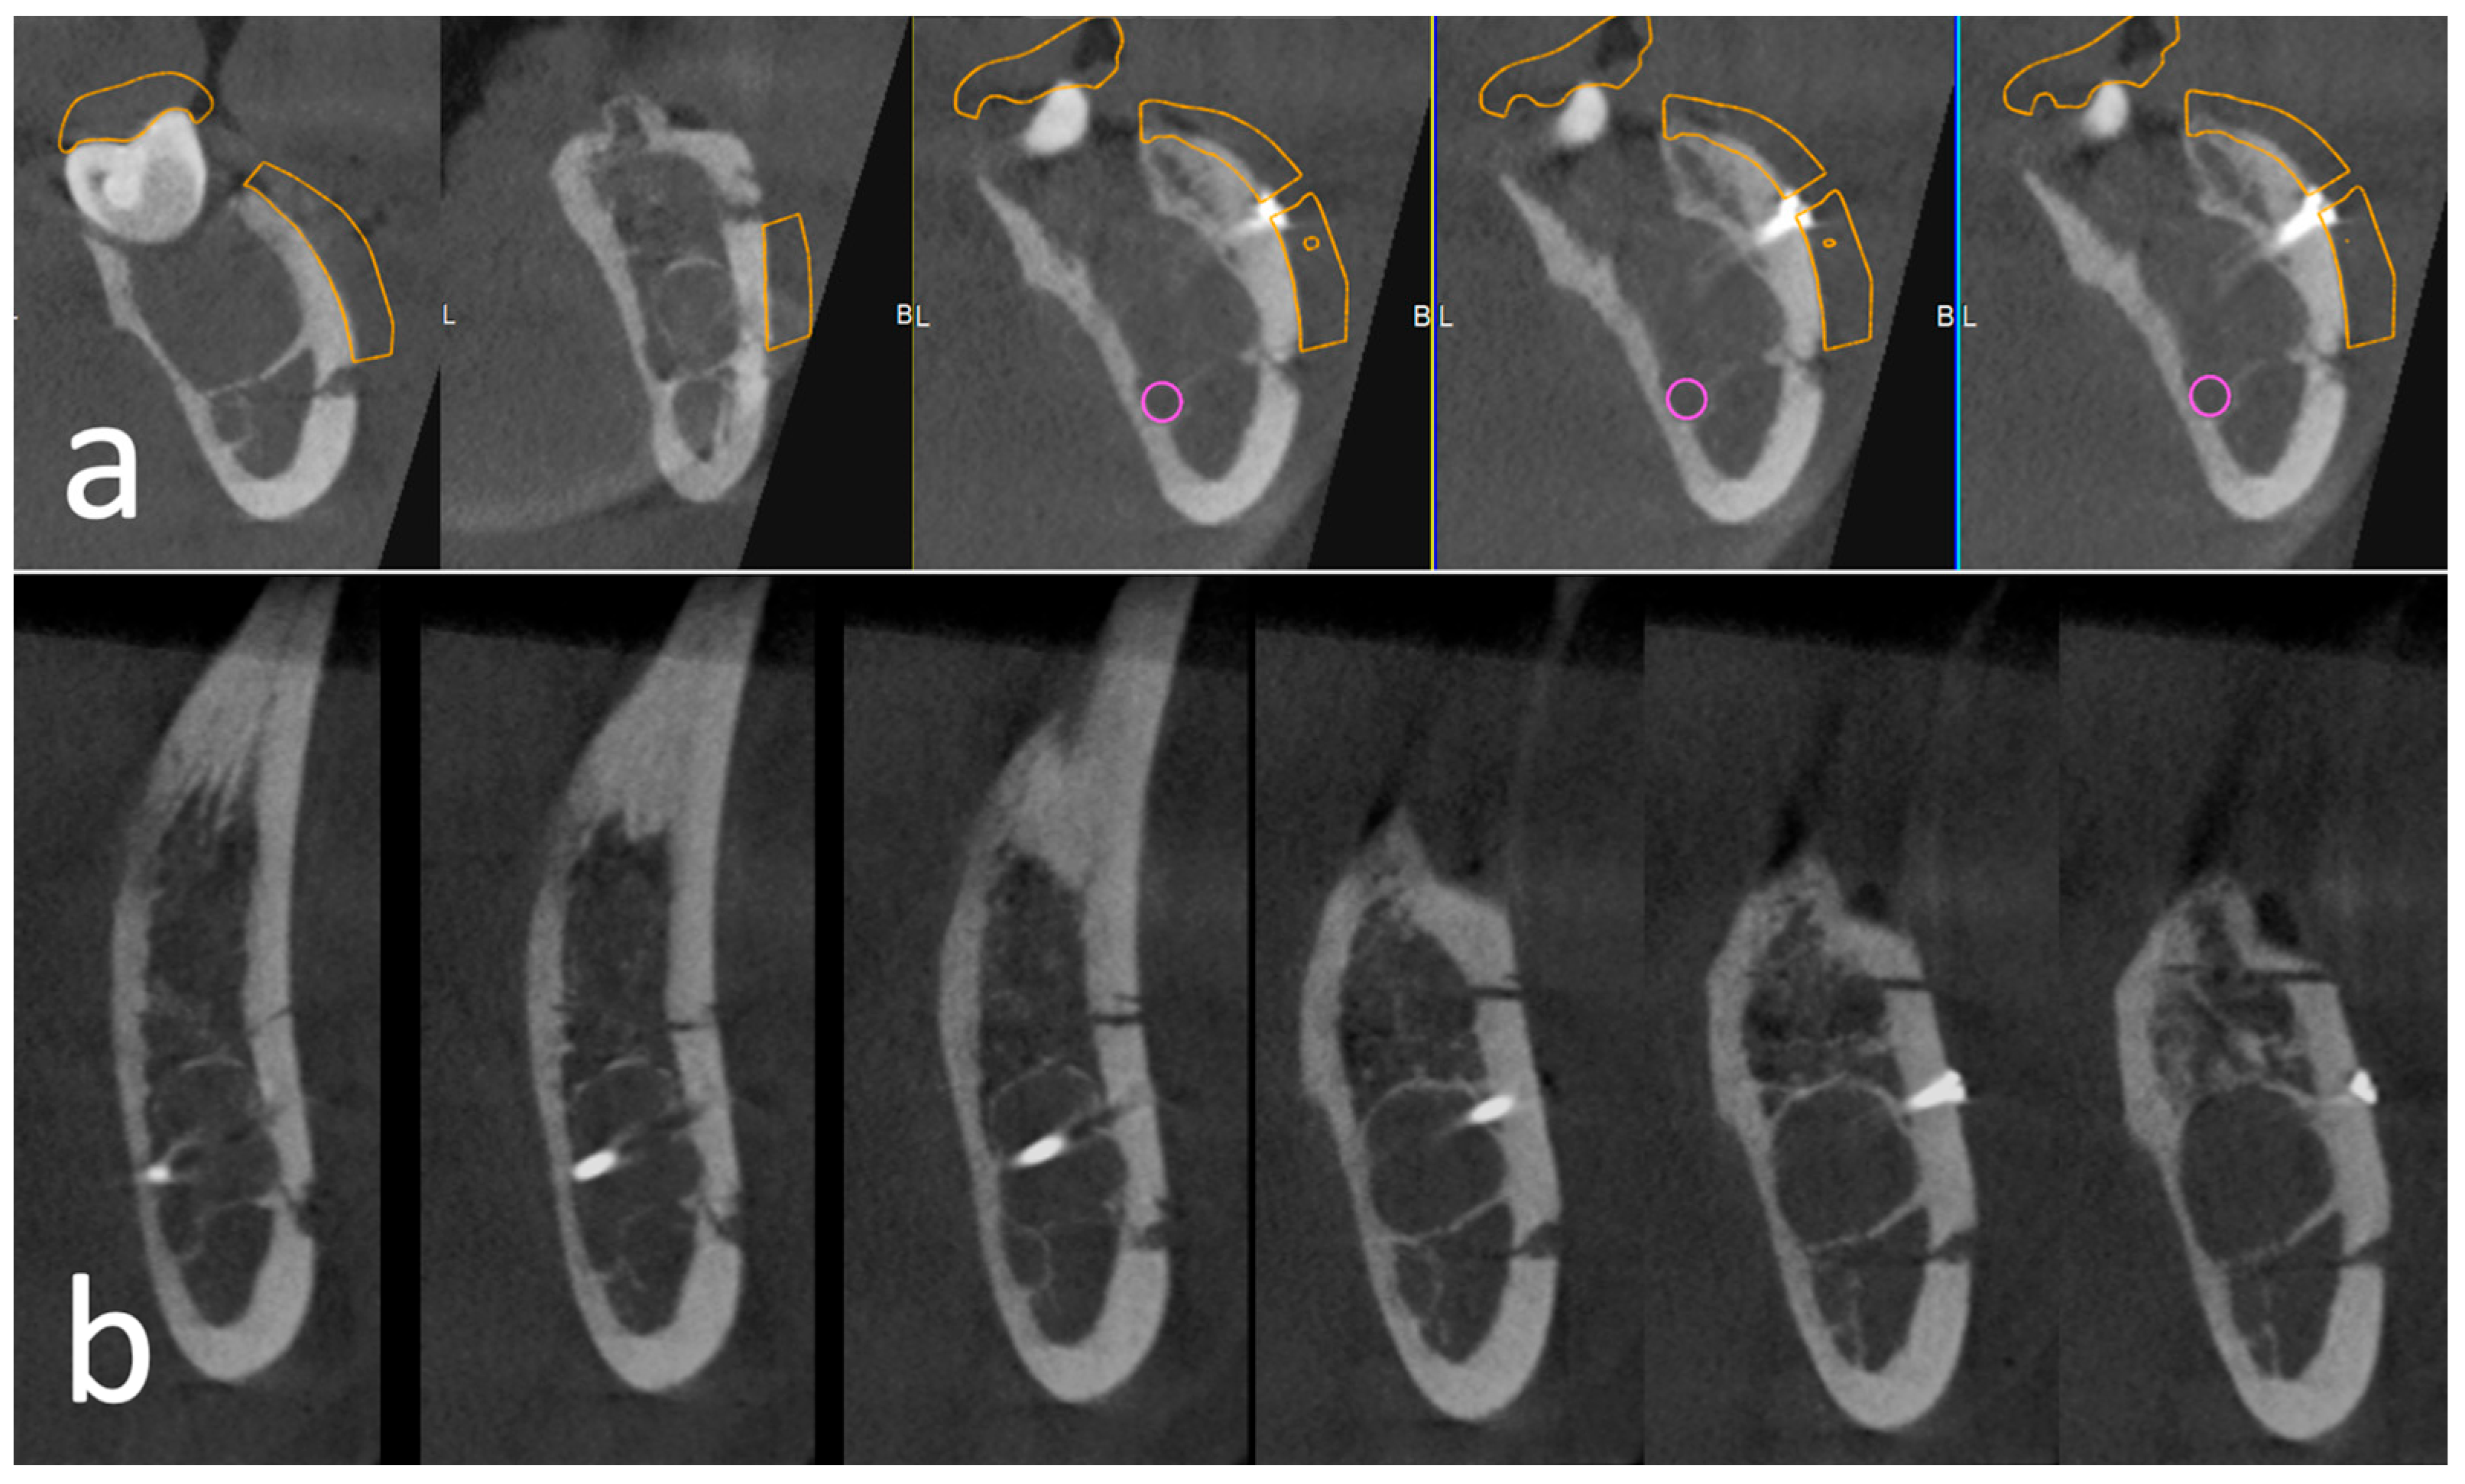

Both patients were discharged with appropriate analgesic and antibiotic therapy and follow-ups were performed at 7 and 30 days postoperatively and after 1 year. In case 1, a histological examination was deposed for follicular cyst. Healing occurred without complications. Immediate postoperative CBCT scans revealed a perfect match between the contours of the template and the osteotomy lines performed. Radiologic follow-up was performed at 1 year with orthopantomography and CT scan, showing the healing of the lesion and the complete mandibular reossification. The reintegration of the bone lid without gaps and the stability of the plate were observed (Figure 5). In case 2, bone healing was detected on the 1-year CBCT scans, even if some areas of lower density could be seen at the level of the extraction socket. The cutting lines were still partially visible and the screw was in place surrounded by high-density bone (Figure 6). In both cases, no symptoms were associated with the screws and plate; hence, there was no indication for a second surgery for their removal.

Figure 5.

Case 1. Postoperative radiological follow-up at 1 year. (a) Detail of the panoramic radiograph; (b) details of the CT scan distally to tooth 37.

Figure 6.

Case 2. Radiological follow-up. (a) Immediate postoperative control: the alignment of the osteotomy with the preoperative planning is visible; (b) 1-year follow-up.